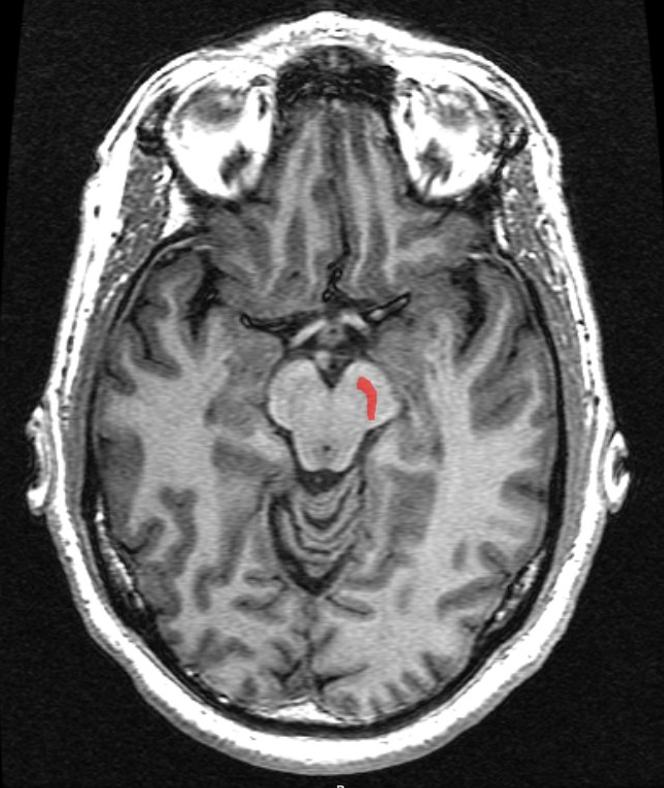

What is the structure called highlighted in red

Substantia nigra